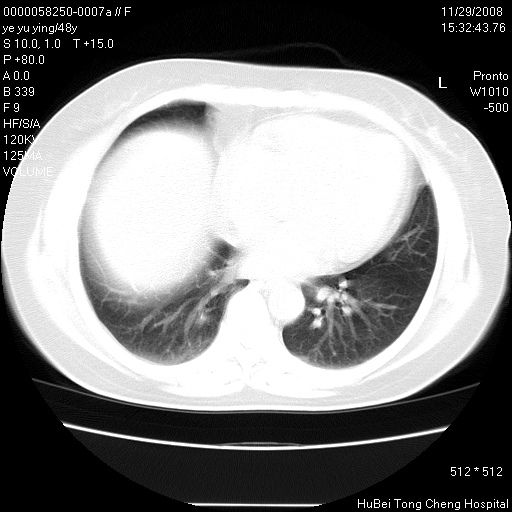

以下是引用zsl6918在2008-11-29 21:47:00的发言:[br]恶性肿瘤病史,转移瘤首先考虑。脂肪肝,胆囊结石。

以下是引用huenhao在2008-11-29 22:11:00的发言:[br]脂肪肝,胆囊结石。左肺病灶建议定期复查。

以下是引用liuyue在2008-11-30 5:44:00的发言:[br]1.左肺病变,首先考虑感染性病变,转移待排;建议治疗后复查。[br]2.肝脏密度普遍减低,考虑与化疗有关。[br]3.胆囊结石.